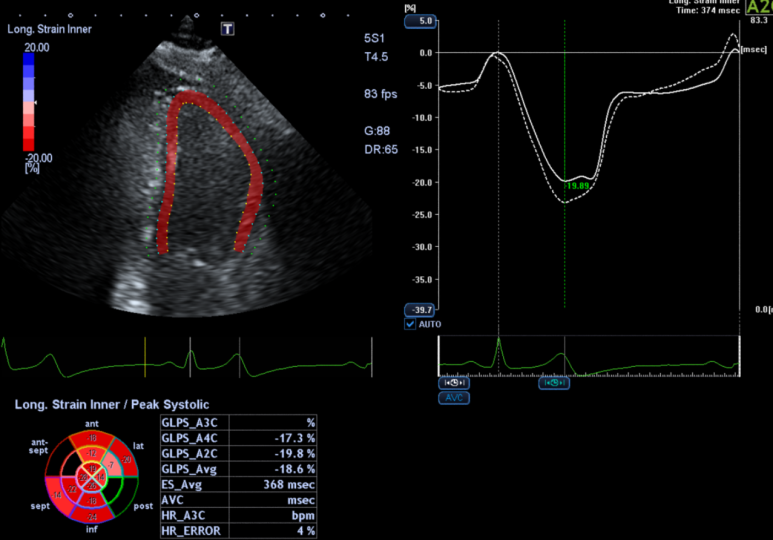

2. 심장초음파

• 심초음파: 정상 심초음파: 정상